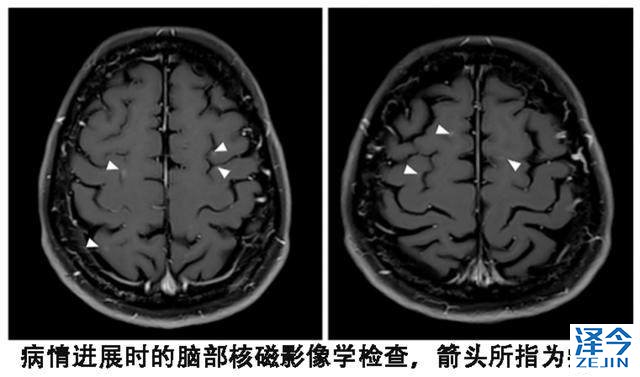

2015年9月,患者进行了视力检查发现双影,根据影像学检查、腰椎穿刺获得脑脊液的细胞学检查,确定脑部病灶进展且出现了脑膜转移。

患者尽管血液基因检测T790M阴性,但是依然换用了第三代靶向药物泰瑞沙(AZD9291),每天的剂量为80毫克,结果出现了奇迹。患者的视觉双影没有了,脑脊液的细胞学检查也为阴性,脑部核磁显示脑皮质损伤有所改善。